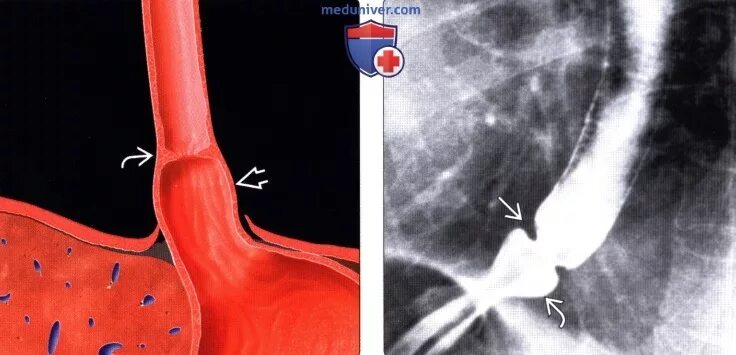

Кольцо шацкого в пищеводе что это